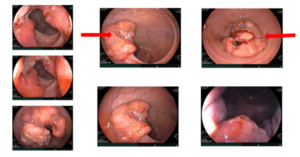

Ca lâm sàng Bệnh nhân mắc hai ung thư nguyên phát: Ung thư phổi không tế bào nhỏ và Ung thư trực tràng

Ca lâm sàng Bệnh nhân mắc hai ung thư nguyên phát: Ung thư phổi không tế bào nhỏ và Ung thư trực tràng GS.TS. Mai Trọng Khoa, PGS.TS.Phạm Cẩm Phương, BSCKII. Lê Viết Nam, BSNT. Nguyễn Bảo Linh Trung tâm Y học hạt nhân và Ung bướu, Bệnh viện Bạch Mai Mở...